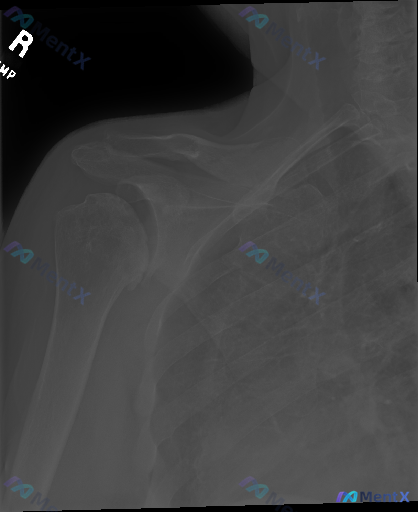

右肩X光见大结节上方高密度影,只想到钙化性肌腱炎就够了吗?

- 骨皮质:肱骨近端、肩胛带、锁骨远端连续,未见明确骨折线

- 关节:盂肱关节间隙、对合关系正常,无脱位半脱位,退行性变不显著

- 软组织:无明显肿胀

- 重点异常:肱骨大结节上方、冈上肌腱附着区域可见高密度钙化影

常规思路可能第一反应是「钙化性肌腱炎」,但这份分析里特意提了几个需要警惕的方向,甚至把某个鉴别放在了更优先的位置。